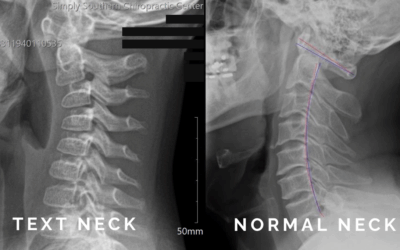

Tech Neck and Text Thumb: How Chiropractic Care Helps Patients of All Ages

How chiropractic care helps with tech neck and text thumb. Learn the causes, symptoms, and safe treatments to relieve pain and improve posture.